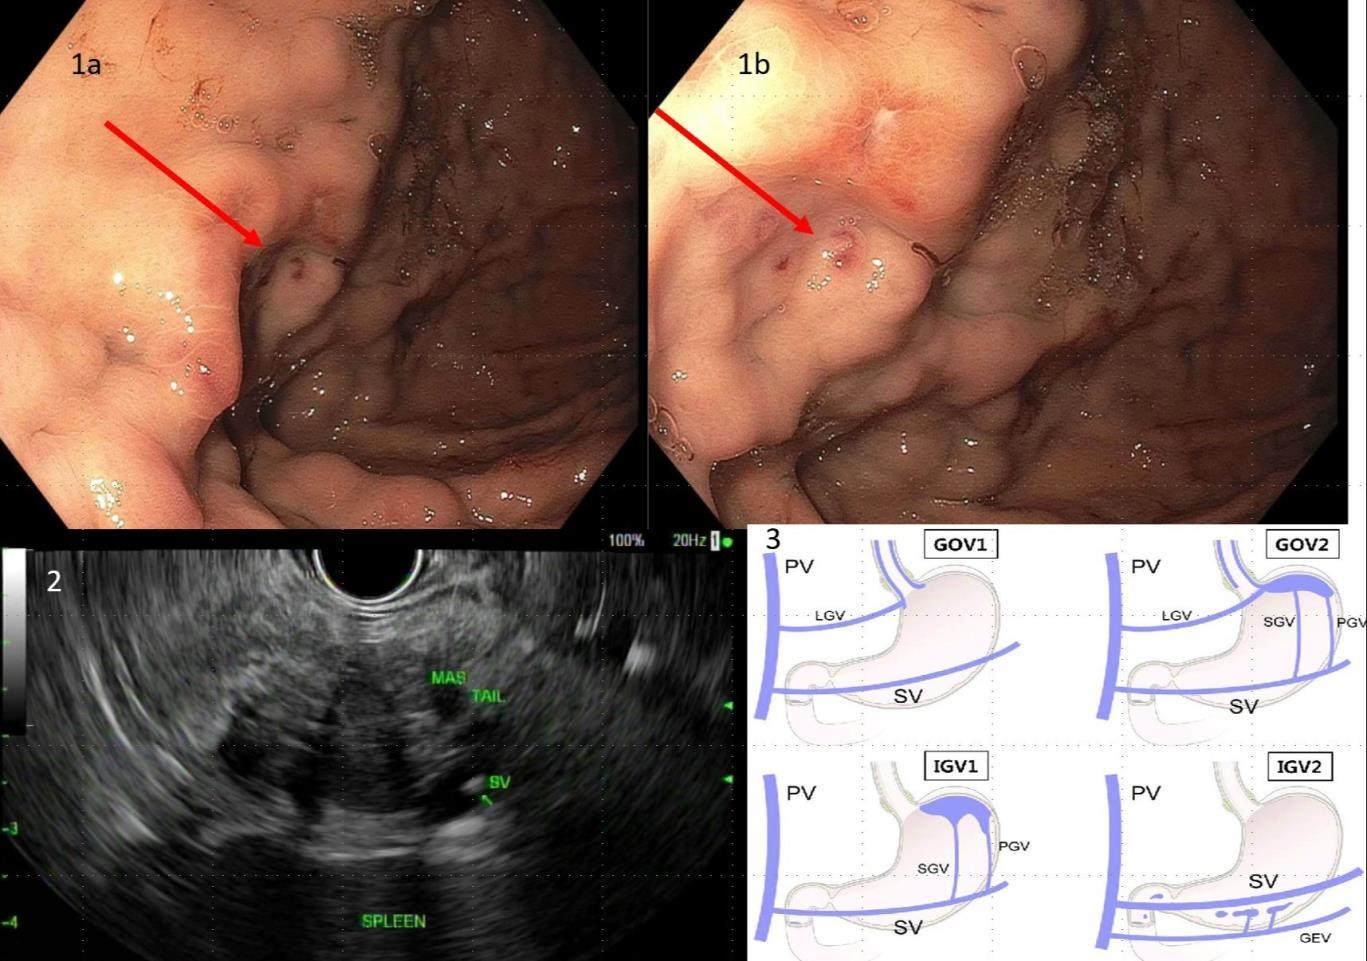

EXTENSIVE SPLANCHNIC VEIN THROMBOSIS ASSOCIATED WITH COMBINED ORAL CONTRACEPTIVE USE

Salvador Caceros Diaz1 , Jonas Marx1